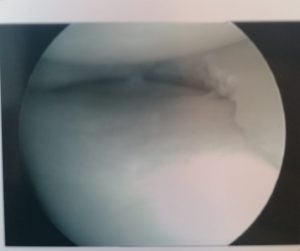

MENISCUS TEAR

The knee can present multiple problems to patients. The most common of these has to be a tear of the meniscus. A meniscus is a horseshoe shaped disc found in the weightbearing compartment of the knee. Each knee has two. The meniscus is typically torn during a twisting motion of the knee with the foot fixed. Symptoms include pain, swelling and clicking.

Treatment usually consists of an arthroscopy with removal of the torn portion. If it is torn in a certain way, the meniscus can also be repaired.

Recovery is short and risks associated are low. See the torn meniscus and the removed tear below.

TORN MENISCUS